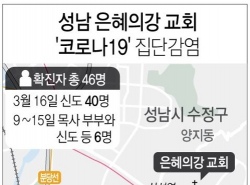

성남 은혜의강 교회, 코로나19 지역사회 확산 우려 고조

성남 은혜의강 교회, 코로나19 지역사회 확산 우려 고조 "46명 집단감염 확인 때까지 자가격리된 신도 7명에 불과" 최초 감염 경로조차 불투명…신도 128명 지역사회서 무방비 활동 (성남=연합뉴스) 최찬흥 ...

| 03-16 12:00